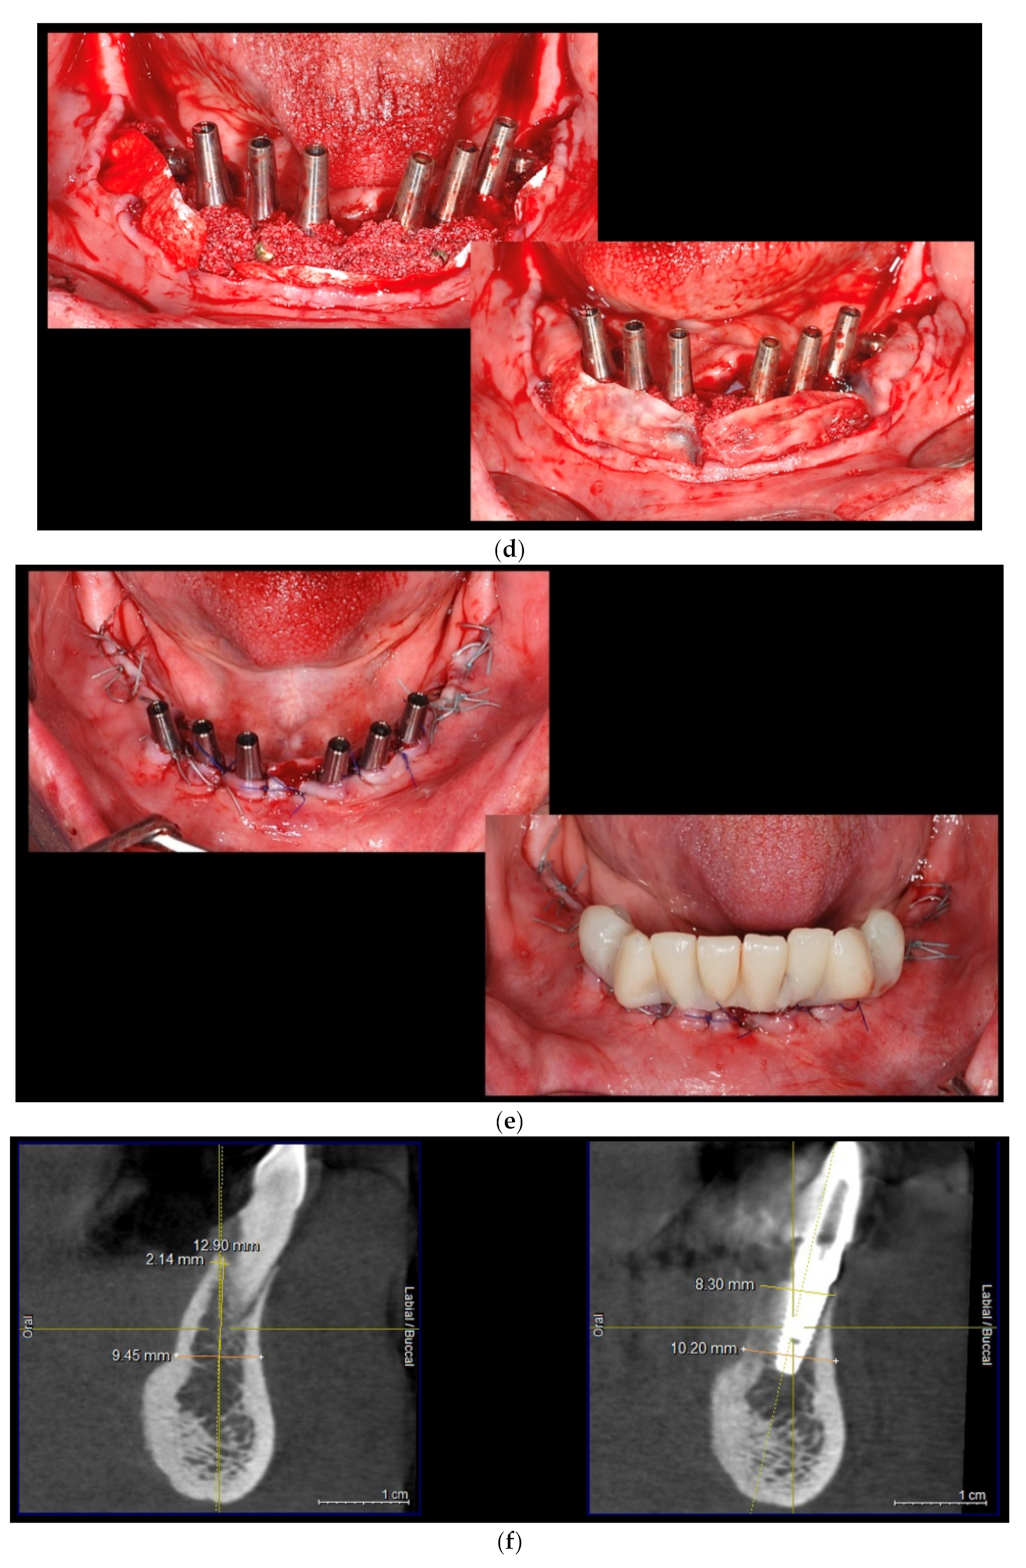

2.2. Description of Surgical Protocol

- (a)

- Dental implants placement simultaneously with alveolar augmentation by S-GBR technique (mixture of autogenous bone with autogenous bone 90:10; porcine pericardial collagen membrane) (test group);

- (b)

- Dental implants placement simultaneously with alveolar augmentation by S-GBR technique (mixture of bovine xenograft with autogenous bone 90:10; porcine pericardial collagen membrane) (control group).

| No. | Procedure | Instruments and Materials | Role |

|---|---|---|---|

| 1. | Local anesthesia | Ultracain DS-Forte (Sanofi, Germany) | Ensure patient and operator comfort |

| 2. | Full-thickness flaps in the alveolar surgical areas | DeveMed GmbH, (Tuttlingen, Germany) | Opened surgical field |

| 3. | Immediate implant placement (length 10–13 mm, diameter 3.5–4.5 mm) | BioSTI implants (Tafers, Swiss) Dentium implants (South Korea) | |

| 4. | Periosteal incisions in flaps areas | Aesculap AG (Tuttlingen, Germany) | The closure of the flaps without tension |

| 5. | Osteosynthesis screws (1.5 mm diameter, 8 mm length) insertion on the buccal face of the bone areas (in 45° angle to the alveolar ridge) | Implantology kits Synthes GmbH, (Zuchwil, Switzerland) DeveMed GmbH, (Tuttlingen, Germany) | Maintain the space for the bone regeneration compartment |

| 6. | The exposed bone surface area will be covered with a small layer of autologous bone, followed by the porcine/bovine xenograft near to the osteosynthesis screw head. The grafted area will be covered with resorbable porcine pericardial membrane | Autogenous bone Bovine xenograft CompactBone, (Dentegris GmbH, Germany) Porcine xenograft Purgo (Purgos Biologics, Seongnam-si, Korea) Porcine pericardial tissue membrane BoneProtect Membrane (Dentegris GmbH, Germany) | Isolated and protected graft in front of the cells from the gingival tissue. Promotion of the gingival healing. Protect the surgical site from gingival dehiscence in the next 3–4 months. Reconstruction of the lateral alveolar bone area |

| 7. | Surgical site suture | Nonresorbable sutures (polypropylene 5.0, Hu-Friedy, USA) | Protection for the reconstructed bone and peri-implant soft tissues |

| 8. | Postoperative care (7 days): antibiotherapy, analgesics, oral cavity rinsing with chlorhexidine 0.5% | Augmentin 625 mg, GalaxoSmithKline Pharma, Viena, Austria); Ibuflam 600 (Zentiva, Lichtenstein) | Postoperative control of the pain and inflammatory processes |

| 9. | Removal of the sutures at 9–11 days postoperatively | ||

| 10. | Second stage surgery: osteosynthesis screws removal at 4 months postoperative |